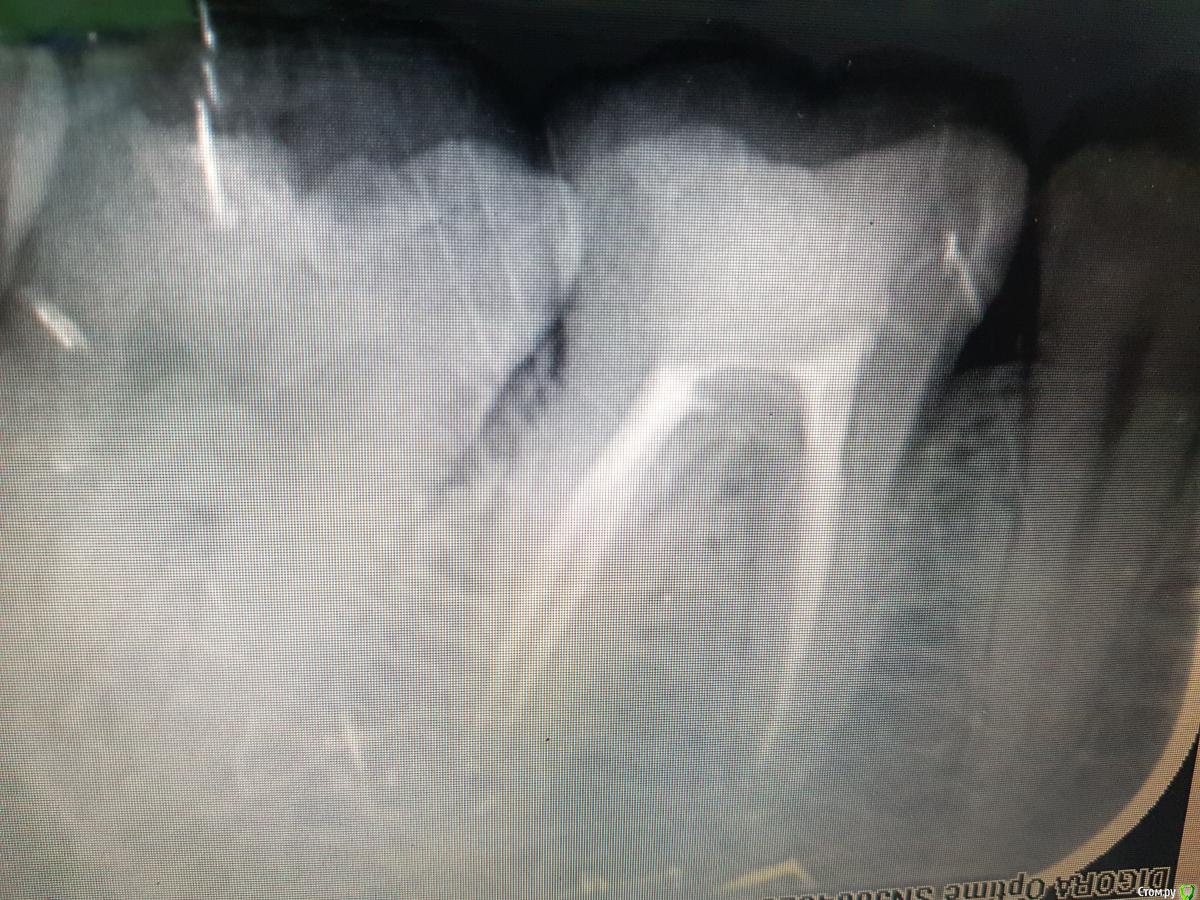

Svetlana-R-13 Опубликовано 7 марта, 2018 Автор Поделиться Опубликовано 7 марта, 2018 Изоляция, обработка mtwo до 25/06, ирригация паркан 3.25, эдта, хлоргекседин 2%. ( снимок только так(( Ссылка на комментарий

Svetlana-R-13 Опубликовано 7 марта, 2018 Автор Поделиться Опубликовано 7 марта, 2018 Ссылка на комментарий